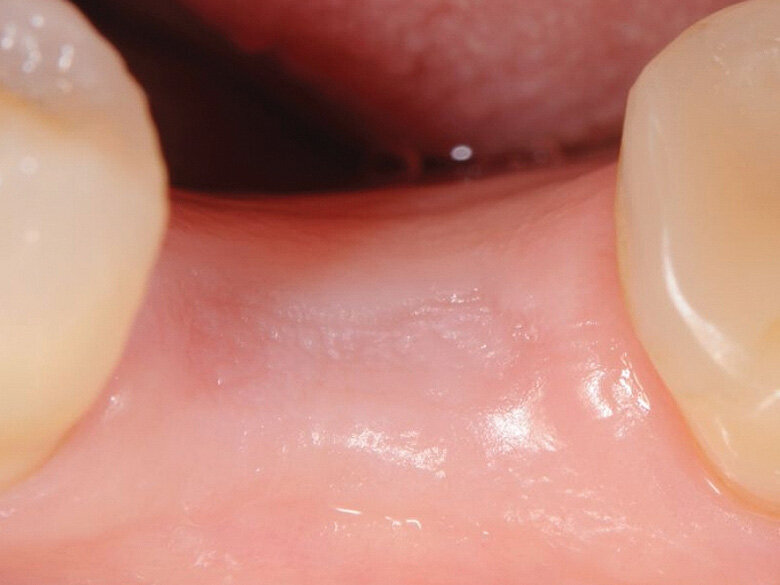

Fig. 2: Four months post extraction. (Photo: Jens Tartsch, DMD)